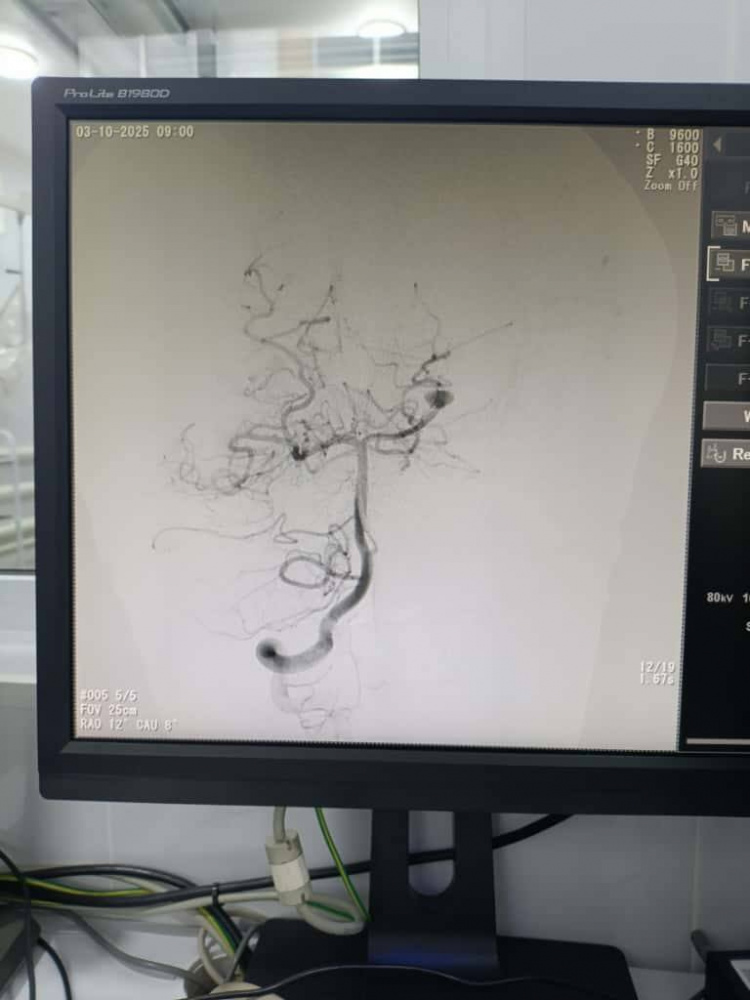

На дооперационном этапе выполнялась ангиографическая диагностика, позволившая определить размеры и расположение сосудистых аномалий и выбрать оптимальную эндоваскулярную тактику для каждого пациента.

При лечении аневризм выполнялась эндоваскулярная окклюзия с сохранением проходимости магистральных сосудов, а при артериовенозных мальформациях — точечная эмболизация патологического узла для предотвращения риска кровоизлияния. Все манипуляции осуществлялись под контролем цифровой субтракционной ангиографии.

После операций проведена контрольная ангиографическая оценка, подтвердившая успешное выключение патологических очагов из кровотока и отсутствие осложнений. Все дети благополучно вышли из наркоза и переведены в отделение реанимации для наблюдения. По данным врачей, состояние пациентов стабильное, осложнений не отмечено, восстановление проходит активно.